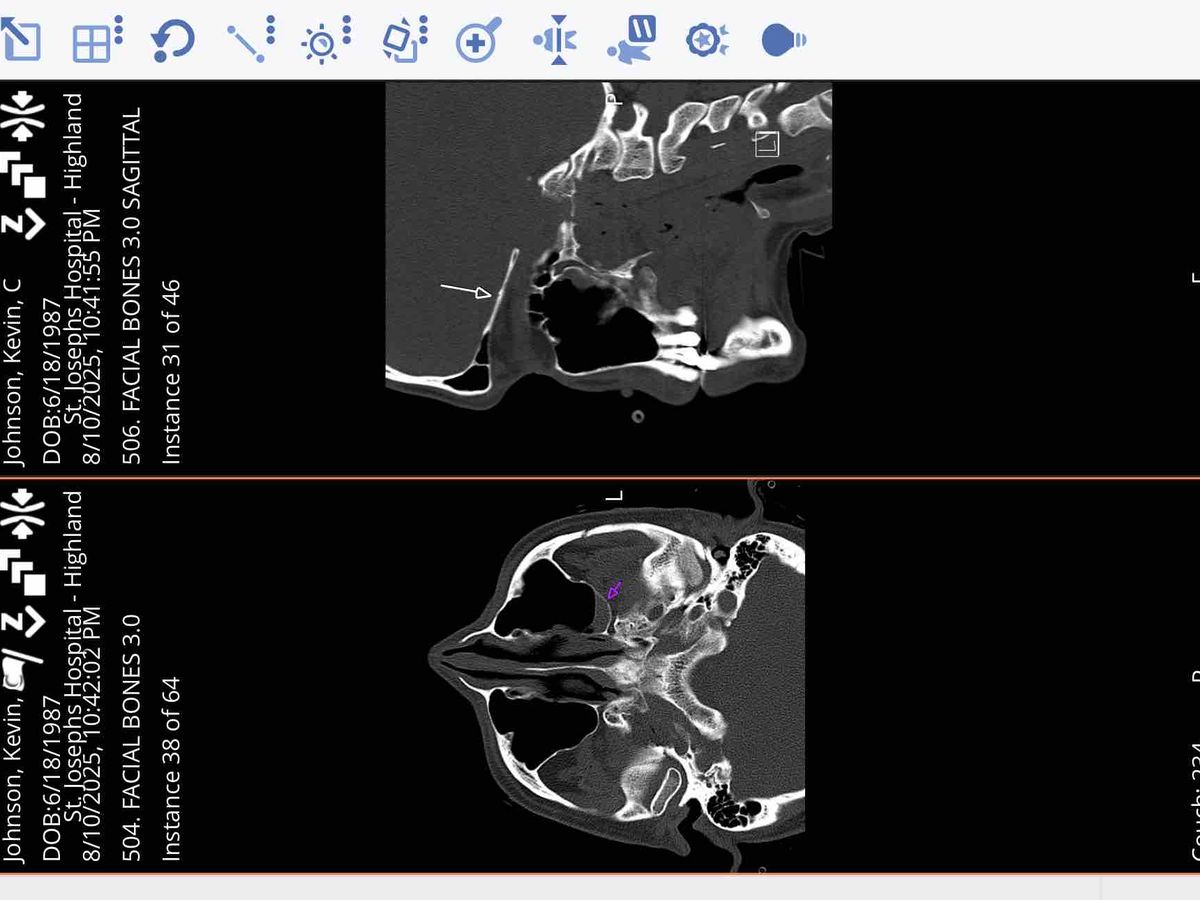

Hi, I’m Kevin Johnson. Not long ago, I was in a serious accident while test-riding my rebuilt e-bike. I don’t remember what happened, but the crash left me with three skull fractures and a brain bleed that could have been life-threatening. The damage to my bike was so severe that doctors believe it may have been caused by a collision with a vehicle, possibly even a hit-and-run. I was airlifted to Barnes Hospital in St. Louis for emergency care, and I’m grateful to be here today and recovering.